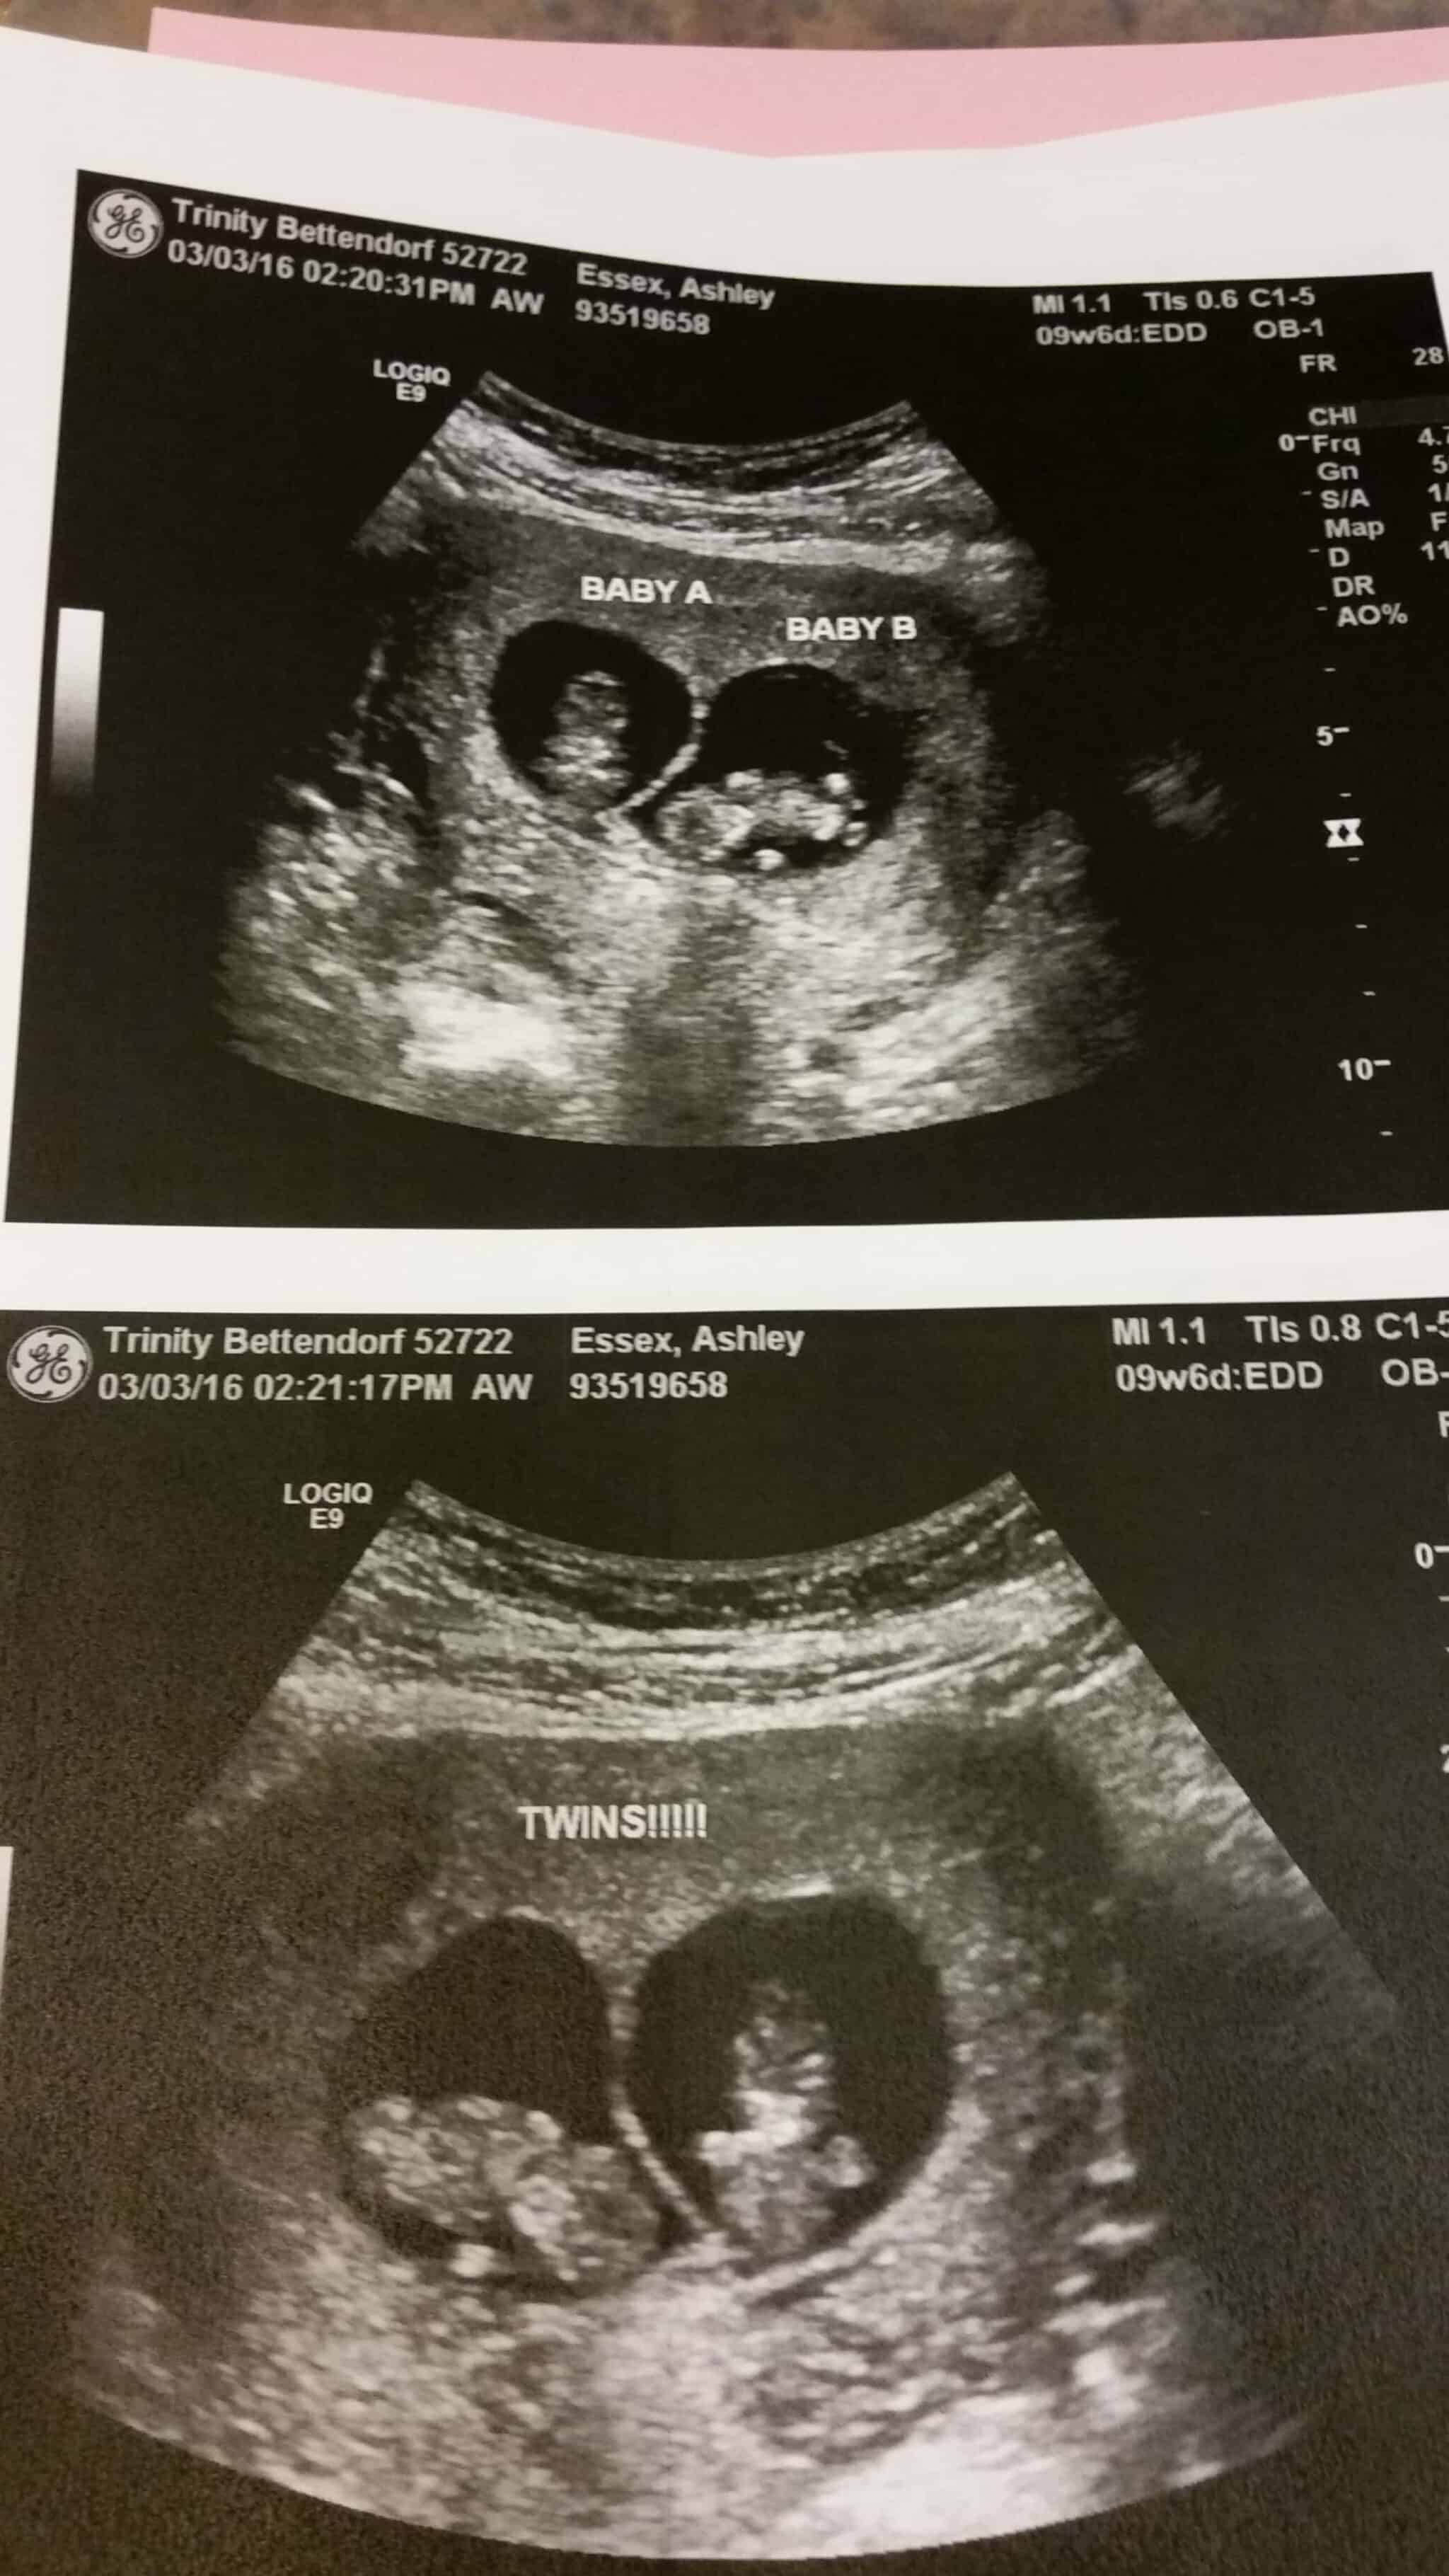

Ultrasound Photos of 10 Weeks Pregnant With Twins